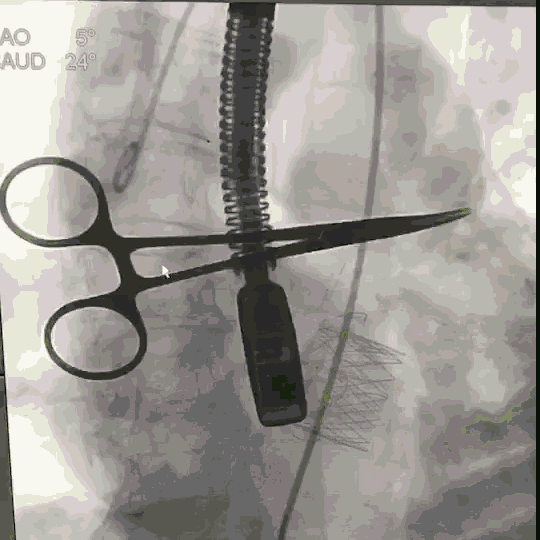

手术在新桥医院杂交手术室内完成,透视下选择心尖处肋间切开,TEE及DSA引导下行心尖穿刺,经心尖送入J-Valve@介入瓣膜并进行释放,瓣膜在定位件引导下进入主动脉瓣区域,释放瓣膜,造影及TEE现实瓣膜位置良好,轻度瓣周漏,术后心脏功能明显好转,循环稳定。手术全程患者生命征平稳。